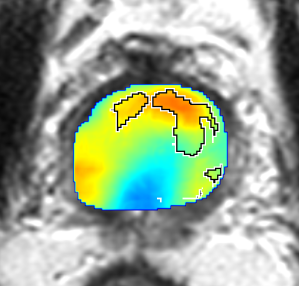

Qualitative Evaluation: Figure 4 shows the same slice as in Figure 2 with aligned T2W, ADC, and histopathology images, and prediction results using current state-of-the-art method [4], our CorrSigNet() and CorrSigNet(T2W, ADC, ) models. It may be noted that [4] fails to detect the cancerous regions on the left and right of the images, while the CorrNet representations alone can identify the cancer regions, and when combined with T2W and ADC images, they predict the cancer regions with high probability. It may also be noted that CorrSigNet(T2W, ADC, ) shows fewer false positives than [4]. This example shows the strength of learning correlated MRI signatures in identifying subtle, and sometimes MRI-invisible cancers. Figure 5 shows more example slices from different patients, comparing the state-of-the-art approach [4] and our prediction results with CorrSigNet(T2W, ADC, ). We note that our model with correlated features (1) can identify subtle and smaller cancer regions, (2) have better overlap with ground truth cancer labels, and (3) have fewer false positives.